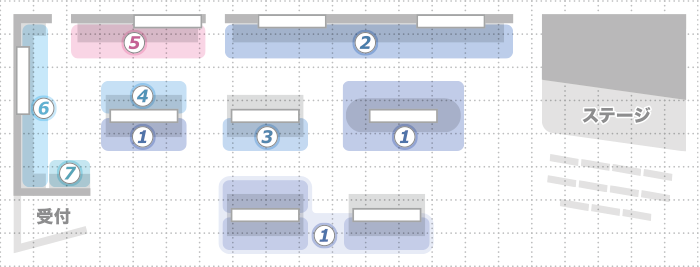

主な展示製品

①AeroDR fine × 画像処理エンジン「REALISM」

発売からご好評いただいている高精細・高画質、堅牢性・把持性などの性能をそのままに「AeroDR fine」がついに3サイズラインアップ。

さらにその潜在能力を最大限に引き出す画像処理エンジン「REALISM」は、体格によらず全関心領域を可視化する被写体毎最適化処理「REALISM tune」に進化。

これまで以上に多様なシーンでの活躍が期待される技術の融合をぜひ当社ブースでご体験ください。

②医用画像管理システム CloudViewing-Pro

データ参照に新方式を採用。サーバ側でデータを集中処理し“いつでも“、”どこでも“、リアルタイムに画像診断やレポート作成を可能とします。

さらにグループ施設間、地域間の連携を想定した患者情報の名寄せ機能も搭載可能です。

異なるIDで管理された同一患者の情報を一元的に管理する「連携ソリューションの決定版」となるシステムです。

当製品は医薬品医療機器等法の認証を得たシステムです。

③ヘルスケアICTサービス infomity

クラウド上に安全に画像データを保管する「データバンクアーカイビング」、撮影画像やレポートなどを医療機関同士で共有できる「連携BOX」、胸部X線画像の鎖骨/肋骨の減弱像を作り、読影を支援する「胸部Bone Suppression 処理」、専門医師の読影報告書を迅速に届ける「遠隔読影支援サービス」などの多彩なサービスで医療機関をサポートします。

当社ブースでinfomityの世界をご体験ください。

④超音波診断装置SONIMAGEシリーズ

高い画像表現力と直感的な操作性で、整形外科領域を始めとした様々な領域で高いご評価をいただいているSONIMAGE HS1 / SNiBLE。

今回新たに、コンパクトでポータビリティ性を追求したSONIMAGE MX1 / SNiBLEybシリーズに加わりました。

ぜひ、当社ブースにて「高画質&シンプル」を追求したコニカミノルタ超音波診断装置「SONIMAGE シリーズ」をご体験ください。

⑤乳がんの早期発見から治療まで Women's Health

I-PACS MAMMO SERIESと Plissimo MGは快適なマンモグラフィ読影環境をご提供。

診断支援システム(CAD)も読影を強力にサポートするオプションです。

進化を続ける SONIMAGE HS1とともに乳がん検診のワークフローを刷新します。

治療分野では、乳房小線源治療用アプリケータ SAVI、植込み型病変識別マーカ Gold Anchor マーカが患者さんのQOL向上に貢献します。

⑥患者様、医療従事者の願い 医療安全

適切な診断、治療が医療機関では求められますが、その手段として適切な環境が整えられているかが非常に重要となります。医療安全のコーナーでは医療現場が日常抱えている安全・安心への課題解決に貢献するため、具体的シーンに沿った様々なご提案を行っています。

輝きのある生命のため、安全安心の医療は患者様はじめすべての医療従事者の願いです。コニカミノルタが考える医療安全へのアプローチをご覧ください。

⑦介護現場のスタッフ業務をワンストップで効率化

ケアサポートソリューション

介護施設での「介助」「移動準備」「記録入力」「記録閲覧」「情報共有」業務が、センサーとスマートフォンを活用した、このシステム1つで効率の良い介護対応が可能になると共にこの介護スタッフの業務効率化によりケア品質の向上・介護スタッフの労力軽減・離職の低減などが期待できます。

また、2018 年度の介護報酬改定に向け優遇処置を活用した介護の労働生産性の向上も期待できます。